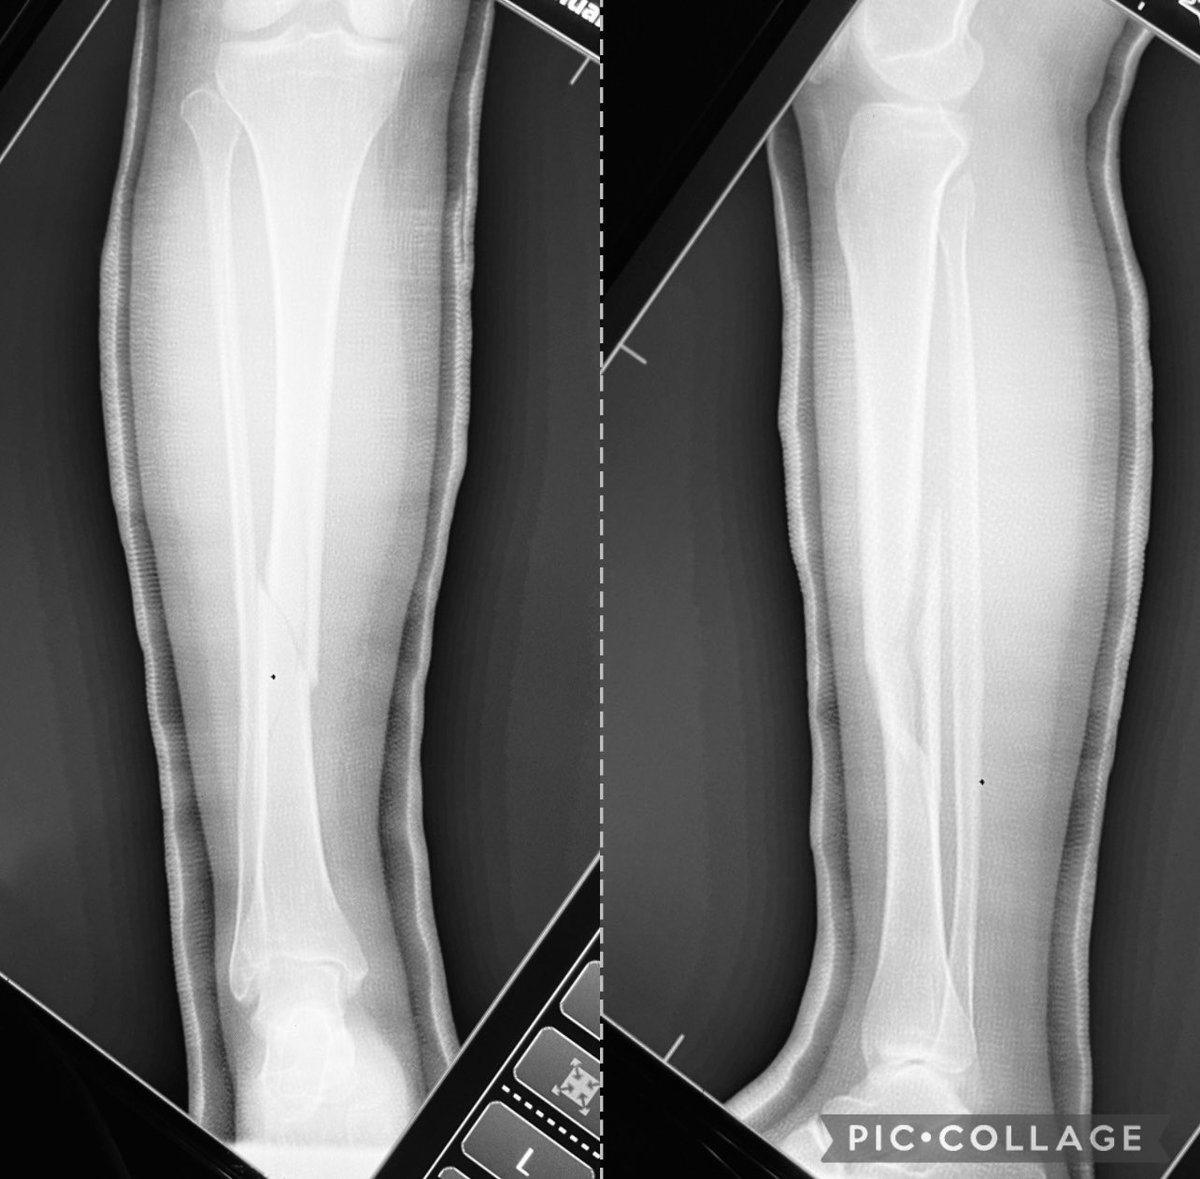

Closed Reduction, Application of Long Leg Cast for Closed Comminuted Diaphyseal Fracture (Middle Third) of the Right Tibia (25/F, Motorcycle accident)

@nongtanch I think is better to operate with a nail. Soft tissues control, less ankle and knee stiffness, and avoid rotational secundary displacement, usually in external rotation and early weightbearing

@nongtanch Proximal fibula is also broken and is more expensive for the patient not to work in 4 months, maybe